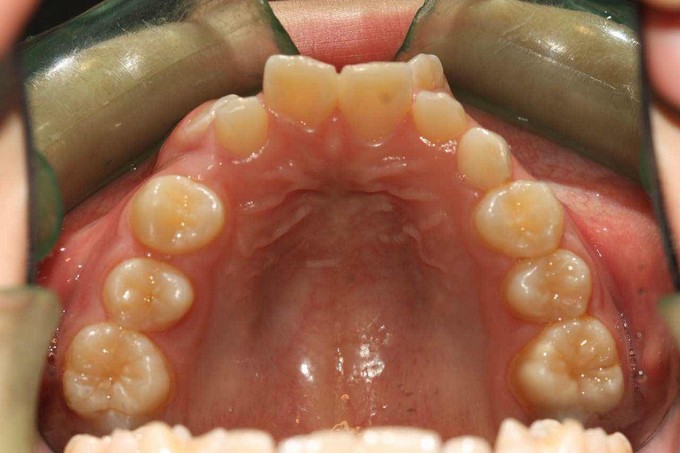

尖牙错位,2过小牙

患者:女,19岁,主诉牙齿不齐,希望矫治。 检查:13根在11和12之间,23根在22唇侧,12和22为过小牙